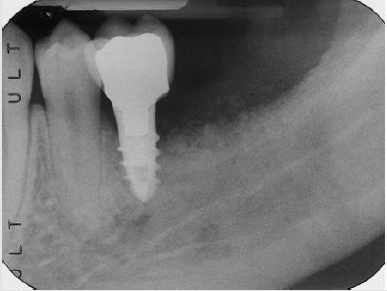

(Biaggini Medical Devices, Arcola, Italy), the ridge showed now a width of 7 mm as compared to the 2 mm at baseline (Figure 10). Three months later the implant was exposed and a healing abutment was connected associating and apical repositioned flap in order to replace the keratinized gingiva buccal to the abutment (Figure 11) One month after complete maturation of the soft tissue impressions were taken in order to fabricate a ceramic crown (Figure 12). Final restoration was delivered about nine months after the beginning of treatment (Figures 13&14) but the radiograph and the clinical picture show how the primary objectives of treatment were met. Bone augmentation in order to accommodate a standard diameter implant in order to re-establish function and proper occlusion. A three year follow up shows a perfect stability of the regenerated area (Figure 15) [5].